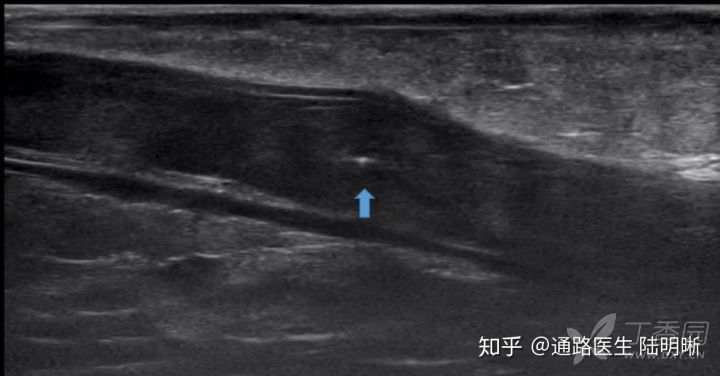

实际超声图如下,确实可见针体横断面回声。

当穿刺针倾斜后,超声图像如下。